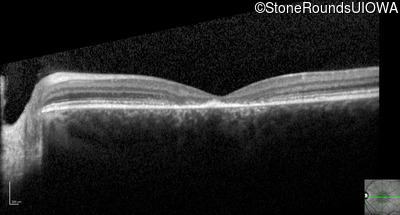

Optical Coherence Tomography - Left - 10/125 -1

Exemplar / OCT Stack

OCT Stack